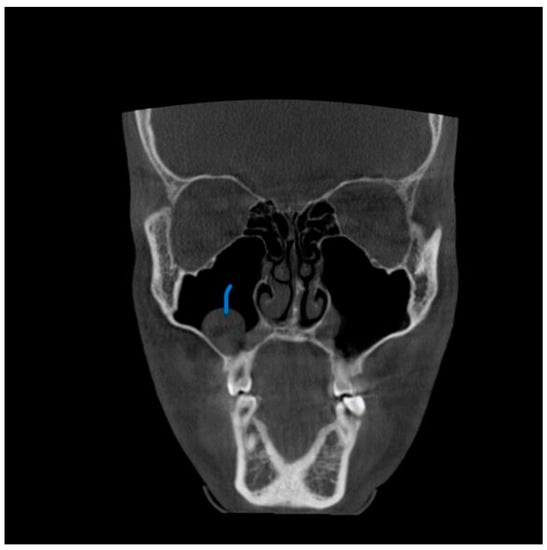

A total of 68 patients had pathologic findings in one or both sinuses, such as mucosal thickening, odontogenic cysts, fracture, hypoplasia, and bone lesions (58.1%) (Figure 1, Figure 2, Figure 3 and Figure 4). Of the 55 male patients, 33 had pathologies, like oroantral communication and inflammatory cysts in either sinus, whereas only 35 of the 62 scans of the female patients revealed radiographically abnormal findings in either sinus. The difference between the male and female patients was insignificant (Table 1).

Figure 4. View from the sagittal plane. The Blue arrow shows the close proximity of the periapical lesion in the maxillary molar and the associated sinus wall thickening.